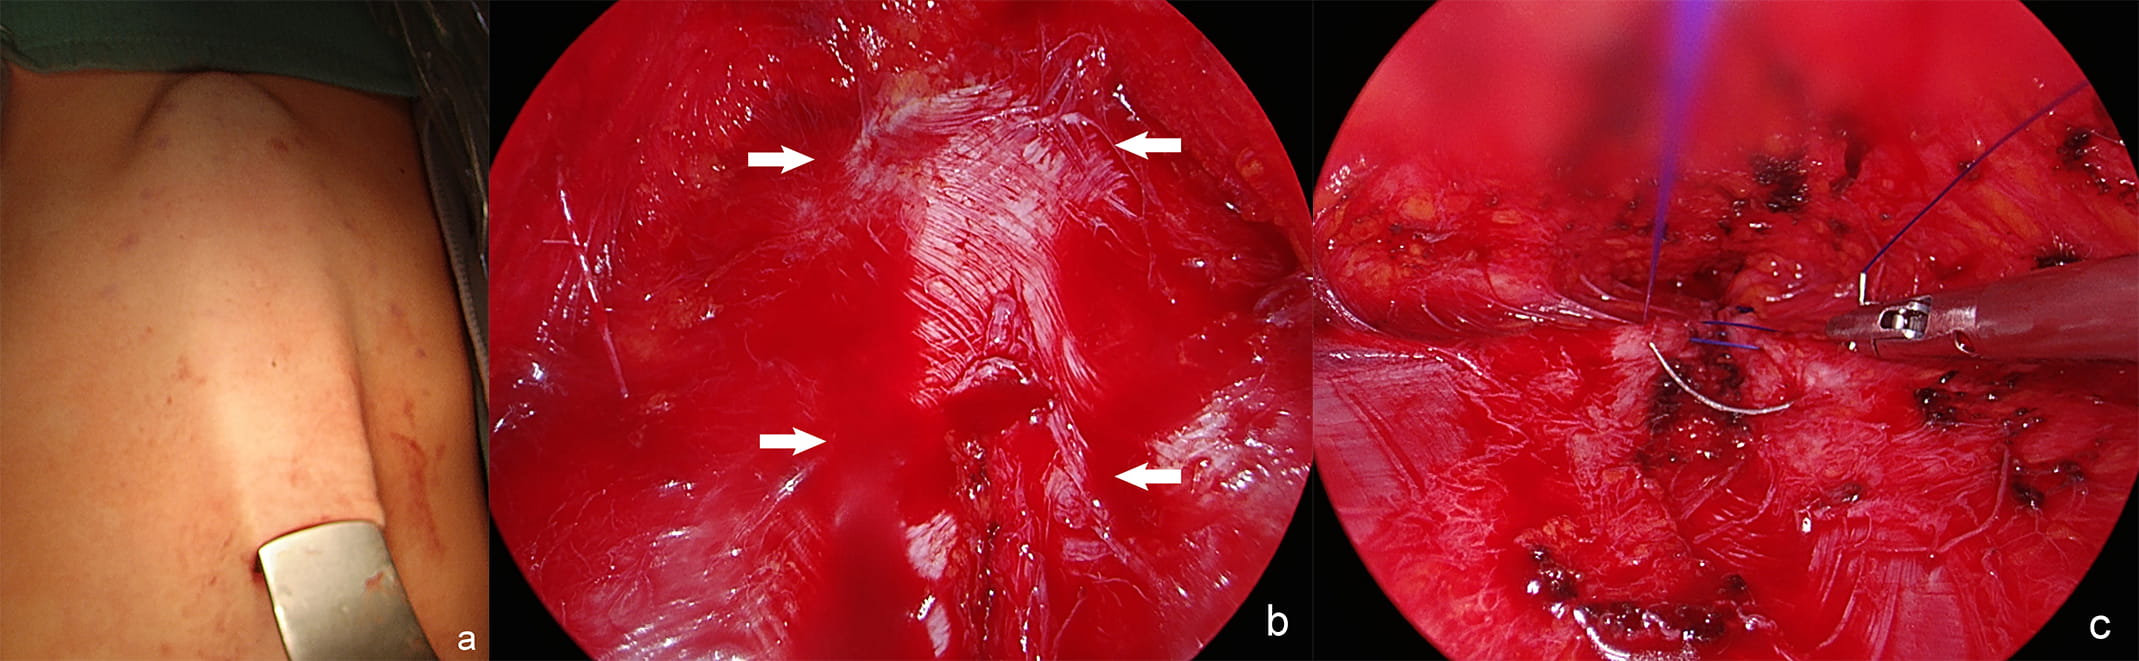

Although cosmetic result of a surgical intervention is of high importance, it is not yet evaluated which surgical technique has the most satisfying cosmetic outcome [3, 13, 30, 41]. To date, despite the importance of cosmetic results, the majority (85%) of published cases are open ones [3]. Though new minimally invasive techniques have been also described. There are also reported some minimally invasive variation of classic procedures that leave minimal scaring, without abdominal cavity opening and risk of incisional hernia (Fig. 5) [3, 7, 27, 28, 39]. Malcher et al. [42] identified nine endoscopic techniques for DRA and ventral hernia repair, including Full Endoscopic Suprapubic Subcutaneous Access (FESSA) [43], Subcutaneous Onlay Endoscopic Approach [44], Pre-Aponeurotic Endoscopic Repair (REPA) [8], Total Endoscopic-assisted Linea Alba Reconstruction [45]. These techniques were differently named, but the surgical concept of subcutaneous endoscopic approach for both DRA and hernia repair was the same [42]. Under endoscopic vision the supra-aponeurotic space is dissected to expose linea alba [46]. Therefore Malcher et al. [42] proposed term Endoscopic Onlay Repair (ENDOR) to unify these procedures. These techniques were effective and safe, allow to resolve the defect without entering abdominal cavity, with good functional and cosmetic results [8]. The most common complication was seroma, pain requiring intervention, hematoma, and surgical site infection [42]. Endo-laparoscopic reconstruction of DRA is safe, effective [29]. Manetti et al. [47] published a pilot study of fully laparoscopic technique, which is a modification of Rives-Stoppa technique. However, two of seventy-four patients had recurrence after six months [47]. Whether these techniques have any functional or cosmetic advantage over open surgery is unclear [3].

Fig. 5.Endoscopic assisted approach for DRA: the retractor lifts the skin above the linea alba. (a) Endoscopic view of the supra-aponeurotic space and exposure of the linea alba. (b) Plication of the anterior rectus sheath with continuous suture. (c) DRA–diastasis recti abdominis, arrows–medial margins of rectus muscles.